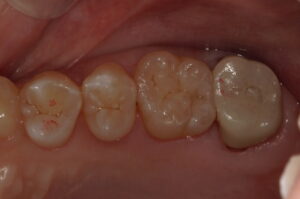

ダイレクトボンディングで修復しました。